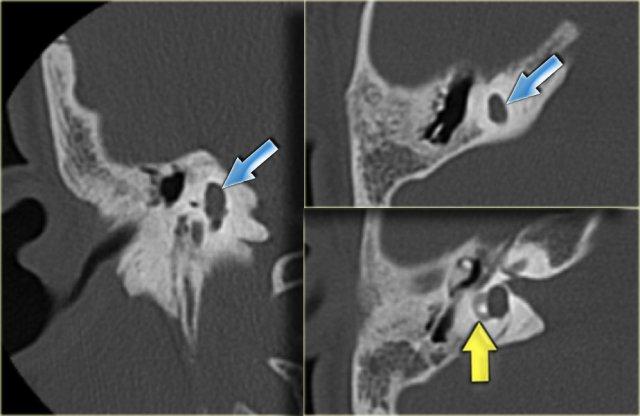

Hành tĩnh mạch cảnh cao

Bên trái là hình ảnh cắt ngang và cắt vành của một bệnh nhân nam 64 tuổi.

Hành tĩnh mạch cảnh nhô lên cao hơn bờ dưới của ống bán khuyên sau (mũi tên).

Hành tĩnh mạch cảnh thường không đối xứng, với hành tĩnh mạch cảnh bên phải thường lớn hơn bên trái.

Khi hành tĩnh mạch cảnh vượt lên trên ống bán khuyên sau, được gọi là hành tĩnh mạch cảnh cao.

Khi vách xương ngăn cách giữa hành tĩnh mạch cảnh và hòm nhĩ bị khuyết, được gọi là hành tĩnh mạch cảnh hở.

Hiếm gặp hơn là hình ảnh túi phình nhỏ – được gọi là túi thừa hành tĩnh mạch cảnh.

Túi thừa hành tĩnh mạch cảnh

Bên trái là hình ảnh cắt ngang và cắt vành của một bệnh nhân nam 50 tuổi.

Phát hiện tình cờ túi thừa hành tĩnh mạch cảnh (mũi tên).

Xoang sigma phồng

Xoang sigma có thể lồi vào phần sau xương chũm.

Xoang sigma có thể bị rách vô ý trong quá trình phẫu thuật khoét chũm, do đó cần được đề cập trong báo cáo chẩn đoán hình ảnh khi phát hiện.

Bên trái là hình ảnh cắt ngang của một bệnh nhân nam 43 tuổi, sau phẫu thuật khoét chũm.

Xoang sigma phồng về phía trước